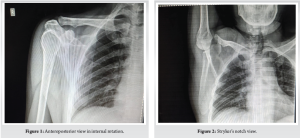

X-ray evaluation

Anteroposterior (AP) view in internal rotation (Fig. 1), and Stryker’s notch view (Fig. 2) revealed the presence of a Hill-Sachs lesion.